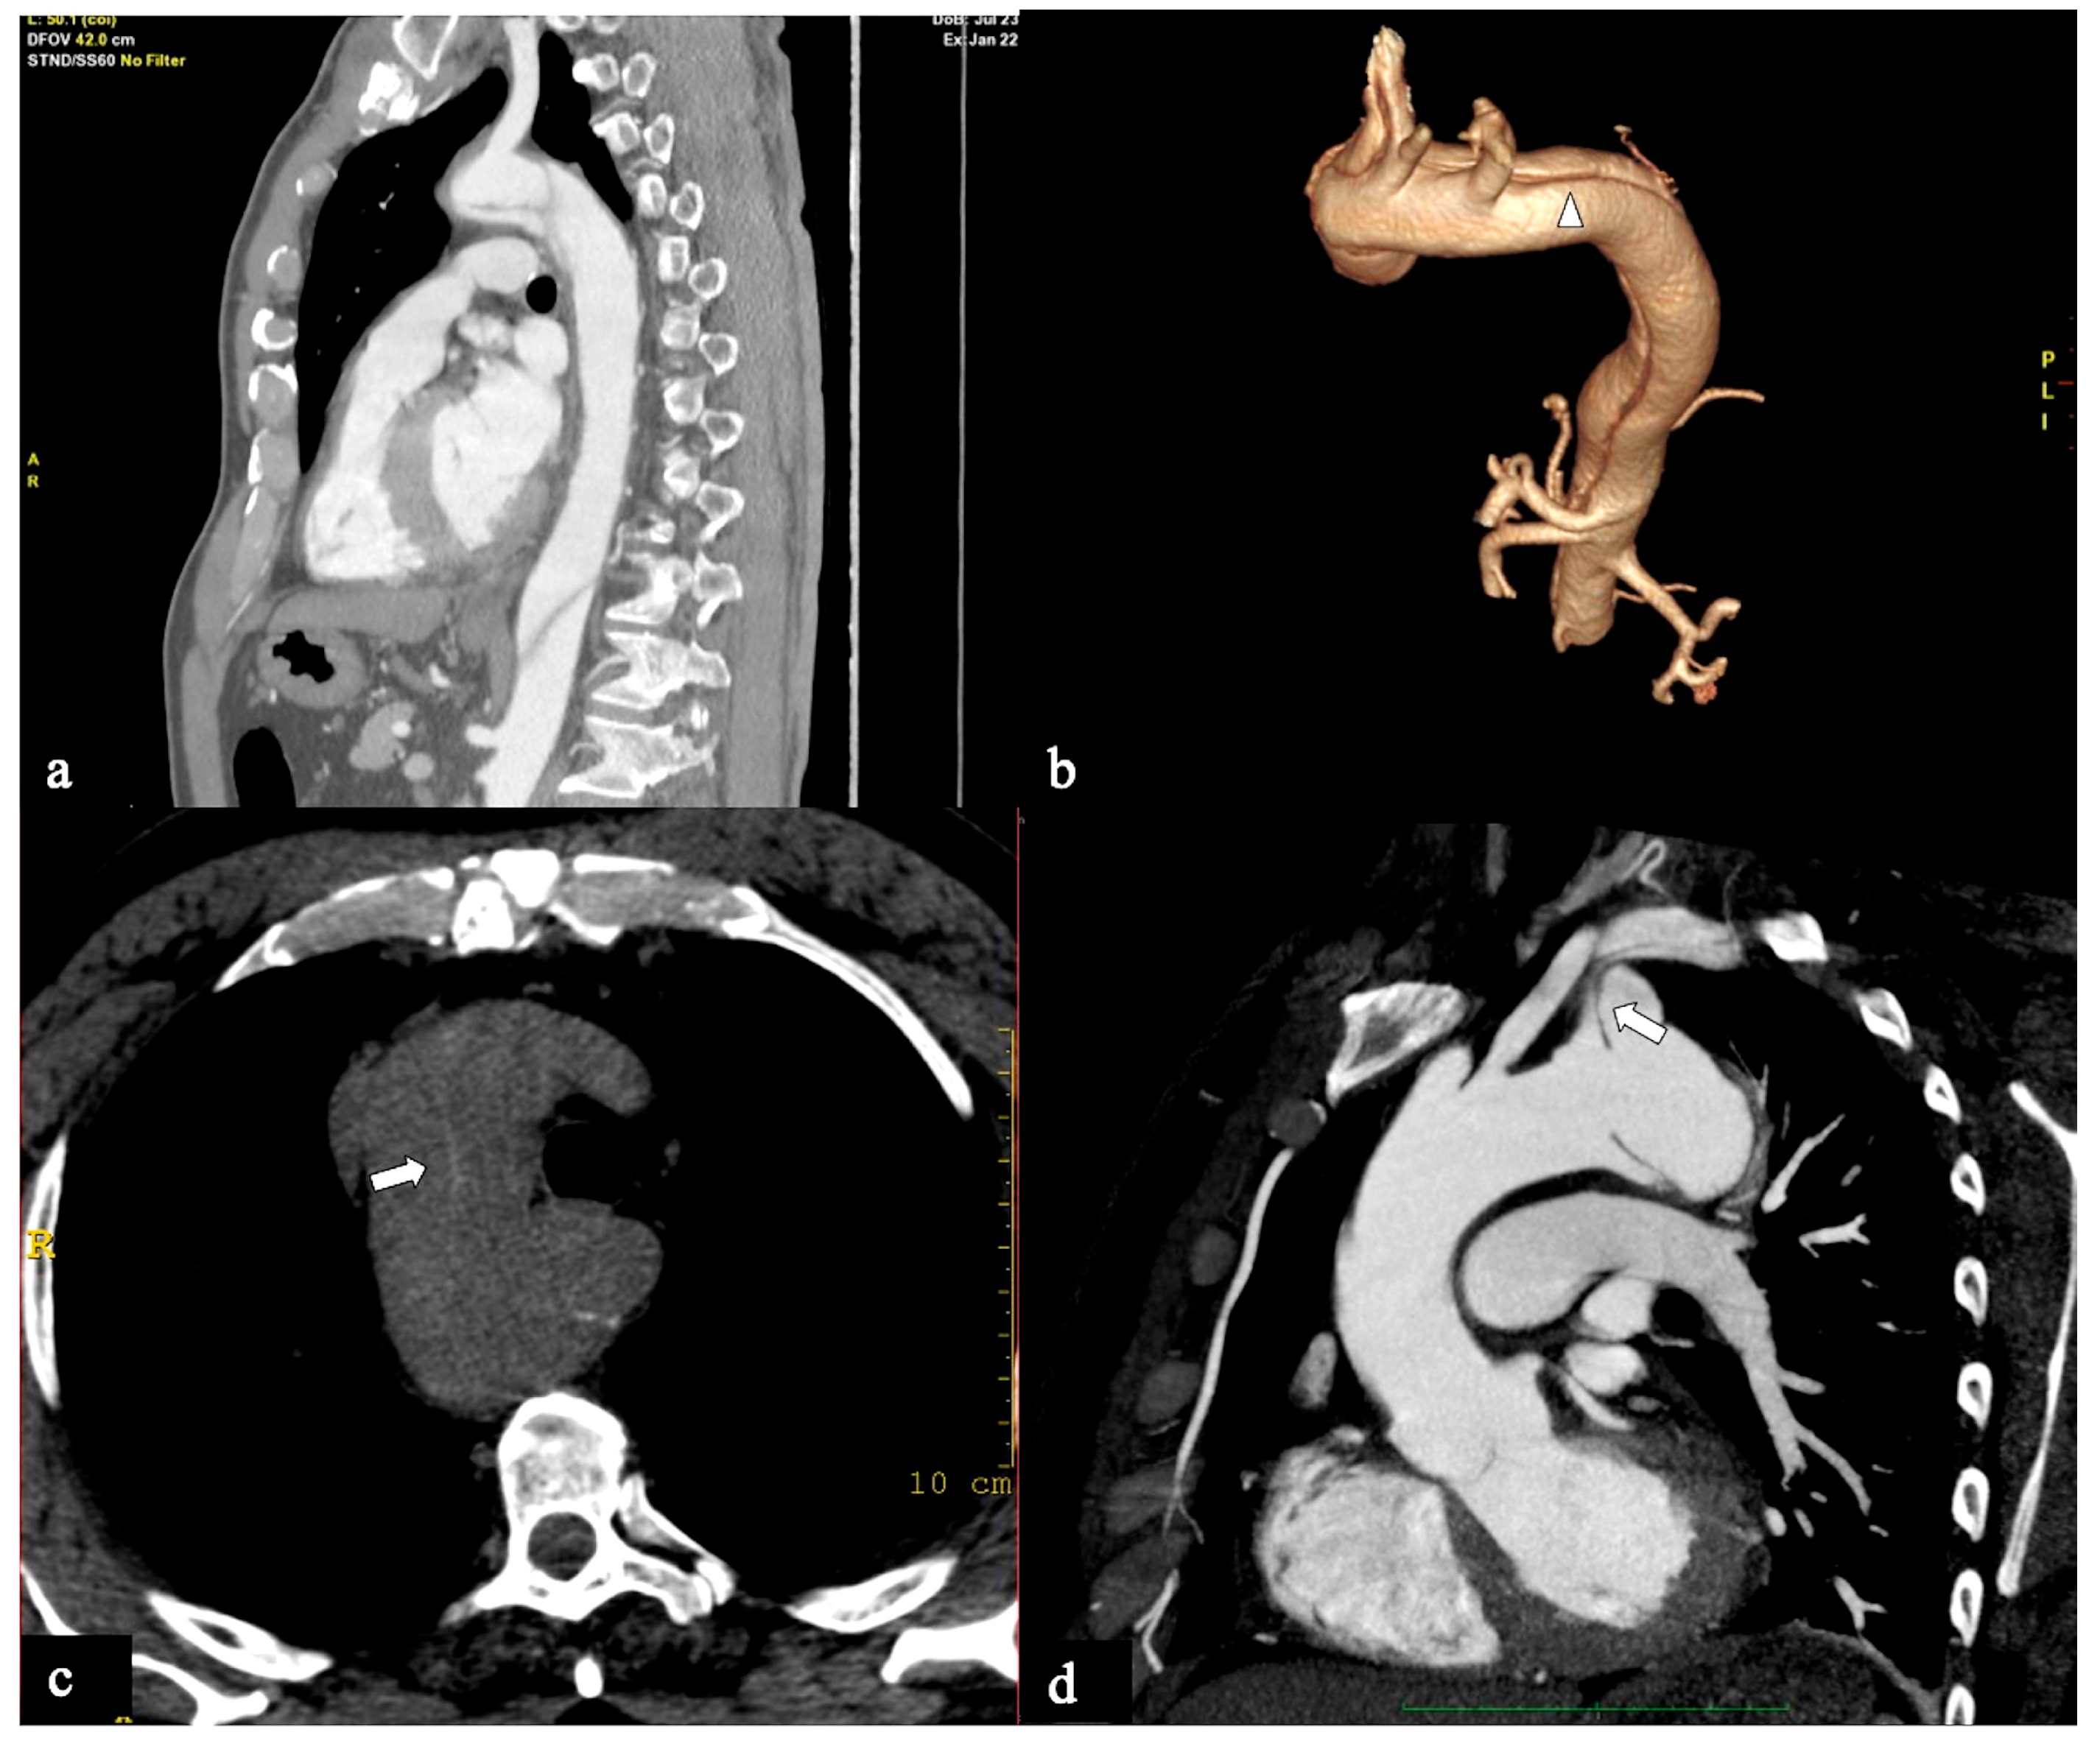

- Configuration 1 (or DTA entry): Among the cohort, 25 out of 36 patients (69.5%) presented with a type B AD or descending-entry type, with the primary entry tear distal to the left subclavian artery (zone 3). The extension of the flap occurred antegradely into the descending aorta, with or without the involvement of the abdominal aorta, and retrogradely into the aorta until the brachiocephalic trunk (BCT) (Figure 3). We describe this configuration as non-A non-B dissection with a retrograde pathway of dissection, as the entry site of the flap is in the descending aorta with retrograde arch involvement. According to Stanford classification, this configuration was present in 14% of type B AD patients. Previous studies have documented DTA entry type to be present between 10% and 25% of patients with acute type B dissection, sometimes as an intramural hematoma [33,34,35]. Patients presenting with DTA entry non-A non-B dissection demonstrated a prevalent origin of BCT and LCCA in 20% and an arch origin of the left vertebral artery in 4%. Among these cases, the distal extent of dissections was observed in various locations: the thoracic aorta in 9 patients, the abdominal aorta in 7 patients, and the pelvic circulation in 9 patients. Involvement of specific arteries was noted, including the left subclavian (n = 5), left common carotid (n = 1), or innominate (n = 1) arteries. Six of these DTA entry patients, who were initially managed with medical therapy, necessitated hybrid or surgical aortic repair within 10 days after the onset of dissection due to persistent pain (3/5), new organ malperfusion (2/5), or rapid aortic growth (1/5). Forty percent of these patients underwent treatment with optimal medical therapy and close imaging surveillance, while 60% received hybrid or open surgical therapy.